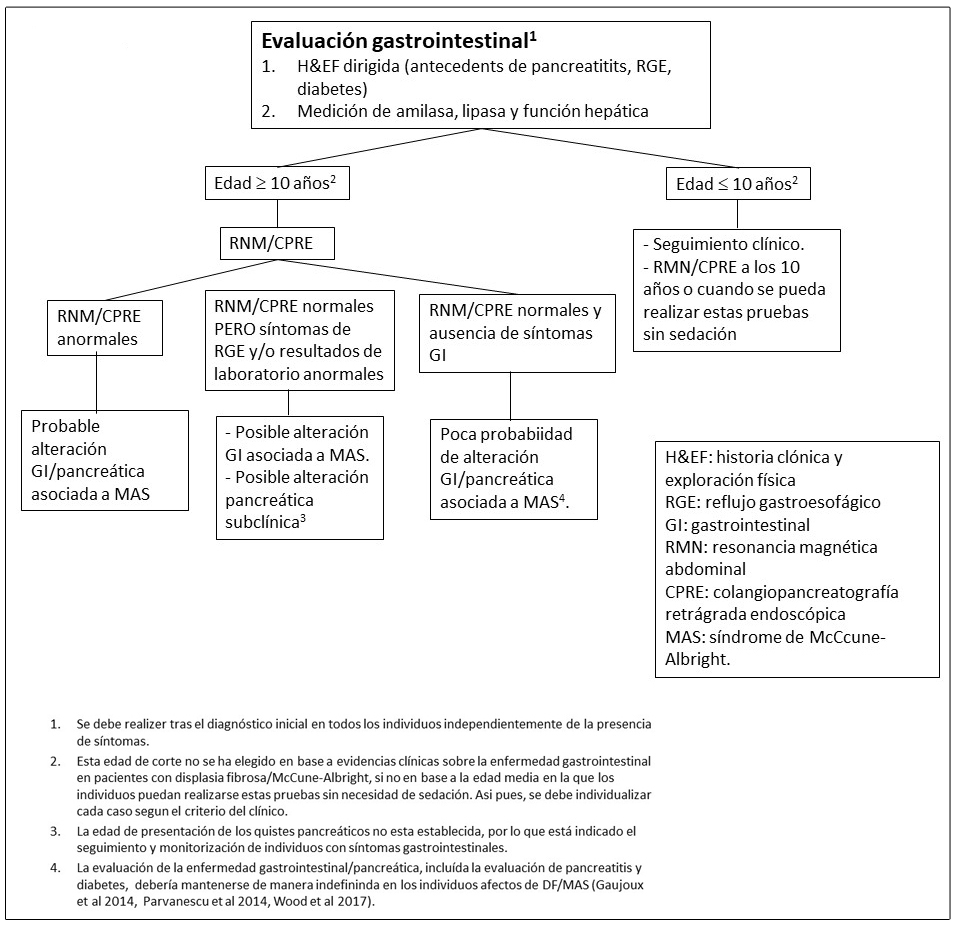

Afectación grastrointestinal.

- El reflujo gastroesofágico se manifiesta en la infancia y puede ser severo.

- Los pólipos en el tracto gastrointestinal superior han surgido recientemente como un hallazgo común en individuos con DF/MAS (Wood et al 2017).

Afectación pancreática.

Aproximadamente un 15% de los individuos con DF/MAS presentan alteraciones pancreáticas incluyendo:

- Pancreatitis

- Neoplasias mucinosas papilares intraductales (IPMN), las cuales pueden presentar diversos grados de displasia (Gaujoux et al 2014, Wood et al 2017).

- Se ha reportado un caso de un paciente con un carcinoma pancreático derivado de un subtipo de IPMN intestinal (Parvanescu et al 2014).

Figura 10. Evaluaciones recomendadas para trastornos gastrointestinales en individuos con Displasia Fibrosa/Síndrome de McCune-Albright